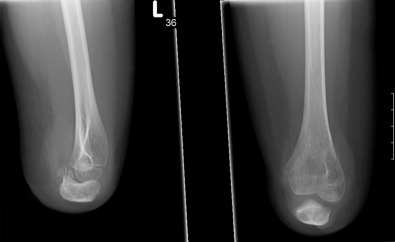

In forearm-level transverse deficiencies, standard x-rays of the elbow and forearm are generally the only diagnostic investigations required ( Fig. 5.4.3 ). Proximal radioulnar abnormalities are commonly present in forearm-level deficiencies. In patients with hand-level truncation, including symbrachydactyly, x-rays are useful to understand the underlying skeletal abnormalities and to assess whether certain interventions such as distraction osteogenesis may be possible for the patient. No specific pre-operative investigations are needed before web space deepening procedures, but close observation of the patient using the hand to play or manipulate objects will guide the surgeon in choosing the appropriate intervention, if any.